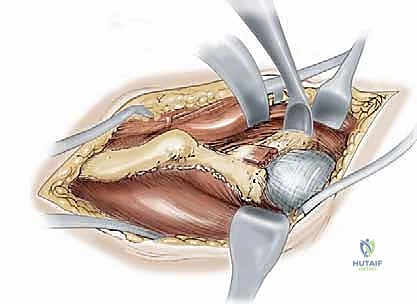

The Surgical Approach and Deep Dissection

We standardly employ the longitudinal anterior Smith-Petersen approach, which provides unparalleled direct access to the anterior pelvis. While a transverse "bikini" (ilioinguinal) incision offers a superior cosmetic result, it can severely restrict access to the deep anterior ischium, particularly in muscular or obese patients. The skin incision begins slightly proximal and lateral to the ASIS, extending distally along the interval between the tensor fasciae latae (TFL) and the sartorius.

During the superficial dissection, meticulous identification and protection of the lateral femoral cutaneous nerve (LFCN) are paramount. The fascia over the TFL is incised, and the interval between the TFL and the sartorius/rectus femoris is developed. The ASIS is often managed via a thin wafer osteotomy, leaving the sartorius and inguinal ligament attached, which facilitates later repair and prevents avulsion. Deep dissection involves elevating the iliacus muscle subperiosteally from the inner table of the ilium, exposing the pelvic brim, the quadrilateral plate, and extending posteriorly toward the greater sciatic notch.

Simultaneously, the outer table of the ilium is exposed by elevating the abductor musculature (gluteus medius and minimus) just enough to visualize the supra-acetabular region and the capsule. The rectus femoris origin at the AIIS is identified; the direct head is typically preserved, while the reflected head may be released to expose the superior joint capsule. Blunt retractors (such as a Hohmann or a specialized Ganz retractor) are carefully placed over the pelvic brim and into the obturator foramen to protect the neurovascular bundle during the subsequent osteotomies.

The Five Interconnected Osteotomies

The hallmark of the Bernese PAO is the sequence of five precise osteotomies.

1. The Anterior Ischial Osteotomy: This is arguably the most technically demanding cut. Working through the interval medial to the psoas tendon, a specialized angled osteotome is guided down the quadrilateral plate to the infracotyloid groove. The cut is made approximately 1.5 cm distal to the acetabular articular surface, directed posteriorly and slightly laterally, intentionally stopping short of complete cortical disruption to protect the sciatic nerve posteriorly and the MFCA laterally.

2. The Superior Pubic Ramus Osteotomy: A blunt retractor protects the obturator nerve and vessels. Using an oscillating saw or osteotome, the superior pubic ramus is cut obliquely, just medial to the iliopectineal eminence. This cut must be complete to allow for fragment mobilization.

- The Supra-acetabular Iliac Osteotomy: Using an oscillating saw, a transverse cut is made across the ilium, originating just inferior to the ASIS and terminating 1 to 2 cm short of the pelvic brim, directing the cut toward the apex of the greater sciatic notch.

- The Posterior Column (Retroacetabular) Osteotomy: This cut connects the medial aspect of the supra-acetabular cut to the posterior aspect of the ischial cut. Using a long, straight osteotome driven down the quadrilateral plate, the cut is angled approximately 120 degrees from the iliac cut, passing completely within the posterior column, remaining extra-articular, and crucially leaving the posterior cortex of the posterior column intact for pelvic stability.

- The Final Liberation: A specialized bone hook or a heavy Schanz pin is placed into the supra-acetabular region of the fragment. With controlled, deliberate force, the remaining intact bone bridges (specifically the posterior ischial cortex) are fractured, fully mobilizing the acetabular fragment.